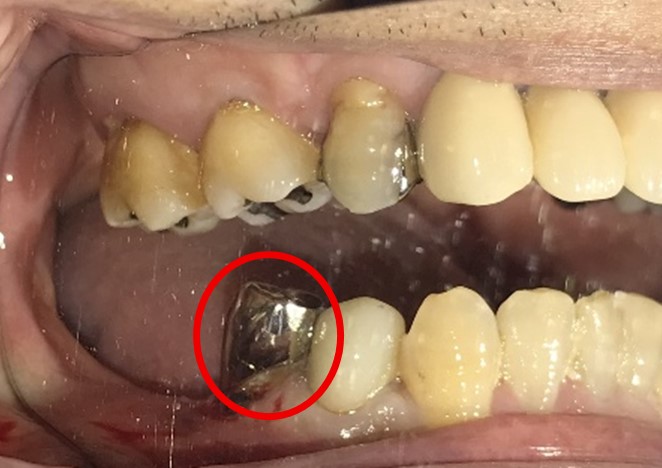

Before

※赤丸を抜歯しました。

After